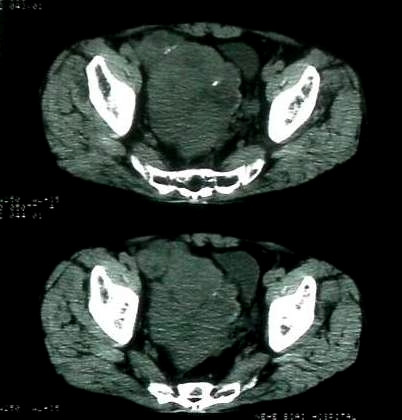

男 60岁,下腹部肿块半年余

腹膜后肿瘤。间叶瘤。

盆腔恶性占位,间质瘤可能性大

病理结果:肠系膜肉瘤

肠系膜的原发性肠系膜肿瘤比较少见,大体可分为囊性和实性两类。囊性肿瘤多为良性。实性肿瘤可以为良性和恶性,恶性肿瘤以恶性淋巴瘤为最多,其次是脂肪肉瘤、平滑肌肉瘤、纤维肉瘤等。恶性肿瘤约占实体肿瘤的6% [1] 。文献资料显示原发性肠系膜肿瘤约7%位于小肠系膜,其中60%位于回肠系膜和肠系膜根部,结肠系膜和阑尾系膜仅占20%左右 [2] 。由于肠系膜肿瘤在临床上不多见,症状无特异性,起病隐匿,早期可无症状,只有当肿瘤增大压迫周围的组织脏器时,才有可能出现相应的症状,并且这些症状常与邻近器官受压有关。腹部包块是主要的症状,临床表现为发热、乏力、腹部隐痛不适和饱胀感、消瘦,偶有呕吐及便秘,当肿瘤出血和囊肿突然增大时,可有腹痛,压迫症状有肠梗阻,下肢肿胀,肾盂积水等表现。体格检查时可触及腹部肿块,且活动度好,尤其是横向移动。b超可早期发现腹块,并可确定大小、性质及部位。x线钡剂灌肠检查,虽然不能提供系膜肿瘤的直接诊断依据,可显示为与肠管关系密切之外在性肿物,并可排除肠管、泌尿系等疾病[3] 。腹腔镜对原因不明的腹痛及性质不明的腹块,既可定性又可定位,其正确诊断率为74% [4] 。肠系膜良性肿瘤和恶性肿瘤的病程长短进行比较,恶性肿瘤绝大多数病程均在半年以内,没有超过2年以上。良性肿瘤大多数病程均在2年以上。这一点在诊断上具有鉴别意义。

病灶形态不规则,偏心性裂隙样坏死,支持恶性病变。来源不好定。感谢反馈结果--肠系膜肉瘤。